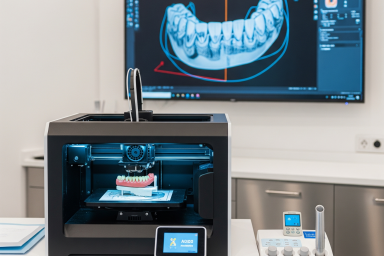

There are factors in implant treatment that are as important as the price: the experience of the dentist, the quality of the materials used, and the hygiene standards of the clinic. For a healthy and long-lasting implant in Alanya, these criteria should be considered. Although price is important in implant treatment in Alanya, the experience of the dentist, the quality of the materials, and hygiene standards are much more decisive factors.